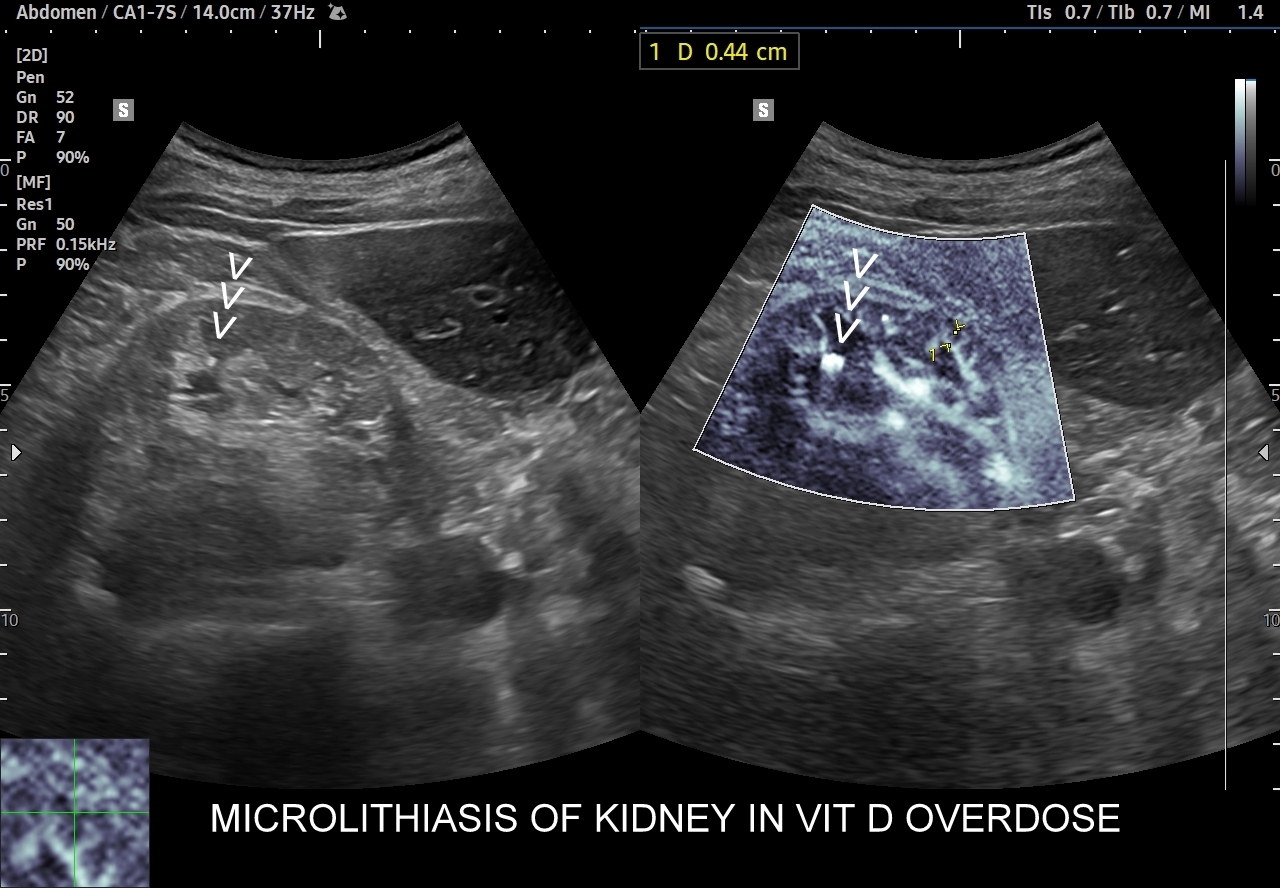

Przyczyny hyperkalcemii i wtórnie hyperkalciurii obejmują zwykle nadczynność przytarczyc, przedawkowanie witaminy D, osteolityczne choroby nowotworowe, długotrwałe unieruchomienie, sarkoidozę. U pacjentów z idiopatycznymi przypadkami kamicy nerkowej w badaniach laboratoryjnych stwierdza się takie zaburzenia jak zwiększone wydalanie z moczem wapnia oraz szczawianów.

Ważnym trybem pomocniczym jest color-Doppler, w którym to trybie uzyskuje się tzw. artefakt migotania, często nawet na bardzo drobnych złogach niewidocznych w trybie B. Uzyskanie efektu migotania jest niestety zależne o jakości aparatury USG, a także od ustawień Dopplera i software’u.

W modalnościach dopplerowskich oprócz prezentacji color-Doppler artefakt migotania pojawia się także w trybie Dopplera spektralnego. Otóż po umieszczeniu bramki dopplerowskiej na złogu uzyskuje się charakterystyczny, dźwiękowy objaw trzeszczenia, a na obrazie wykresu wypełnienie sygnałem całego spektrum częstotliwości.